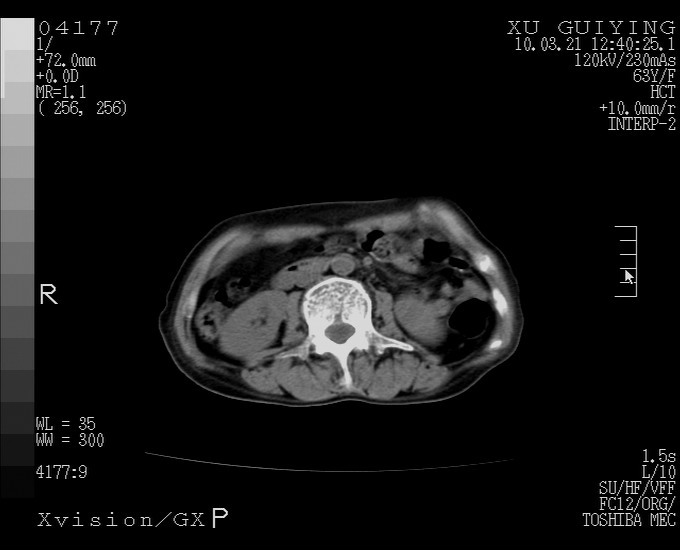

标题: CT25230:女,63岁,萎缩性胃炎病史,患者明显黄染,不能进 [打印本页]

标题: CT25230:女,63岁,萎缩性胃炎病史,患者明显黄染,不能进

怎么没有增强呢?胆囊那么大,密度有些高啊。

慢性胆囊炎,胆囊占位不排除,建议增强或彩超。

考虑胆囊炎 不除外泥沙样结石

胆囊体积增大,胃窦壁增厚

胆囊体积增大,密度不均匀,结石不除外;胃壁增厚,考虑胃癌,建议增强。

胆囊体积增大,密度增高,较均匀,外缘也较光滑,应考虑胆囊炎。因为胃未充盈,不好说壁增厚。肝左叶及脾门处见低密度灶,有可能是血管瘤,不排除囊肿。建议超声检查或强化。

这就是江湖人称的“内科黄疸”, 肝内胆汁淤积症(ic)?